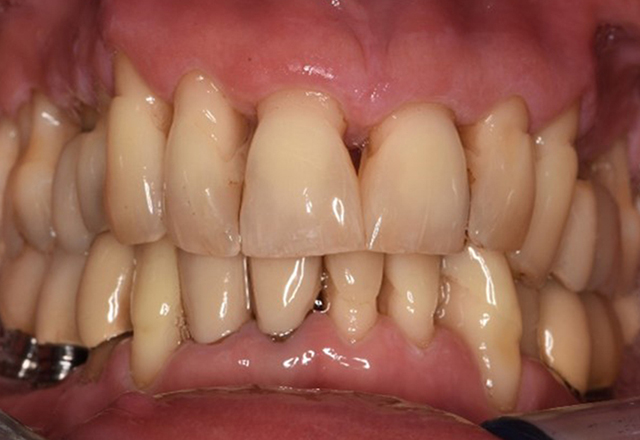

Der gesunde Patient mit parodontaler Vorerkrankung & Periimplantitis

Ein 52-jähriger Patient stellt sich zur Präventionssitzung vor. Der Patient hat keine Allgemeinerkrankungen und nimmt keine Medikamente ein. Er hat verschiedene zahnärztliche Versorgungen und zudem zwei aktive kariöse Läsionen. Außerdem verfügt der Patient über vier Implantate (2., 3. und 4. Quadrant). Es zeigt sich eine parodontale Vorerkrankung (Stadium IV, Grad B). Derzeit herrschen stabile parodontale Verhältnisse, lediglich am Implantat regio 36 zeigen sich Sondierungstiefen (ST) von 5 mm. Zudem lässt sich eine Gingivitis feststellen. mehr Infos